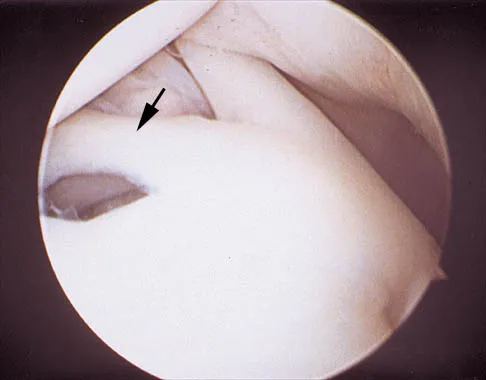

A 24-year-old athlete has a painful right shoulder. Figure 30 shows an intra-articular photograph that was obtained through a posterior portal during arthroscopy; the labrum is indicated by the arrow. Based on these findings, management should consist of